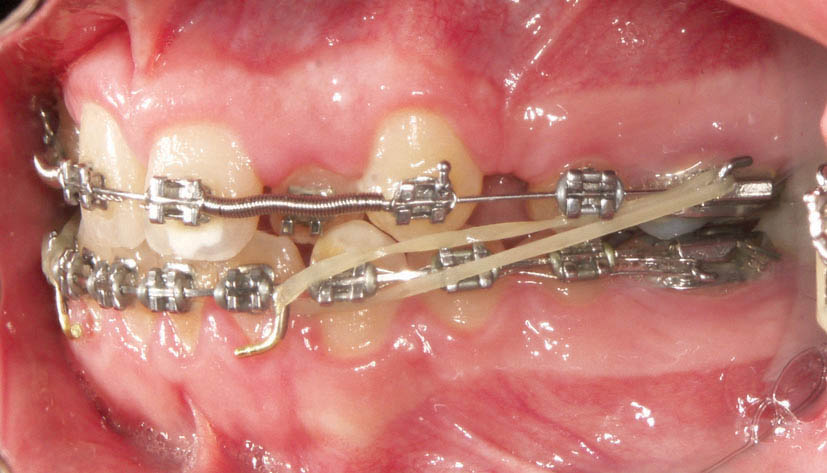

وقتی رابطه مولری کلاسII است و در هر دو فک فاصله داریم، لاتکسها را از سگمنت خلف پایین به سگمنت قدام بالا میاندازید تا هم خلفیهای پایین جلو بیایند و رابطه مولری را اصلاح نمایند و هم قدام بالا عقب برود و اورجت را اصلاح نماید. به این نوع لاتکس اصطلاحاً الاستیک کلاسII میگویند (شکل 39-4).

شکل 39-4: الاستیک کلاسII